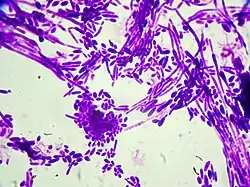

| Gram stain of Candida dubliniensis cells (1000-fold magnification) | |